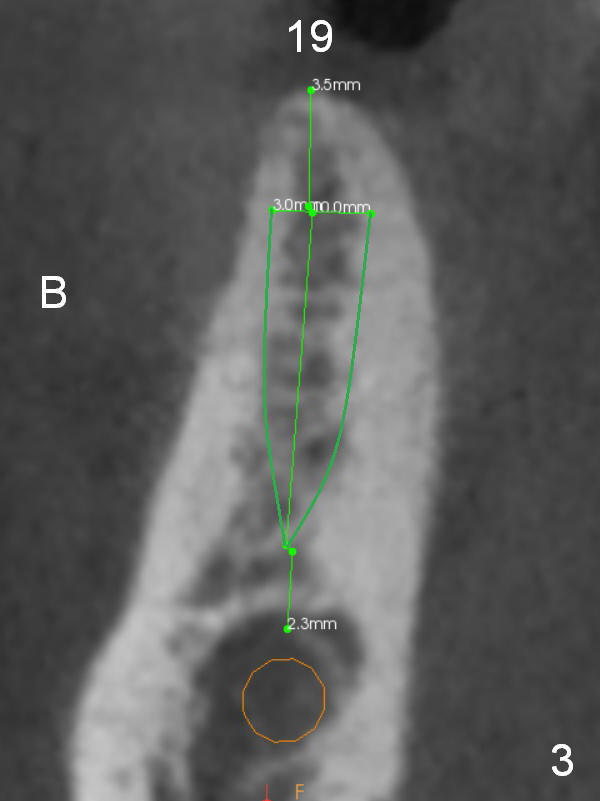

A 71-year-old man requests restoration at #18-20 (Fig.1). Placing implants at the narrow ridge of the sites of #18 and 19 is quite challenging (Fig.3,4), as compared that at #31 (Fig.5). Since the bone density at the crest is high (1200-1500 u), use a surgical high speed fissure bur for sectioning the crest, followed by BEB at 11 mm. It appears safer to place 1-piece implant (Fig.3) than 2-piece one (Fig.4). Since the total mesiodistal distance for #18-20 is 18 mm, splinting the three-units should be a sound treatment option.